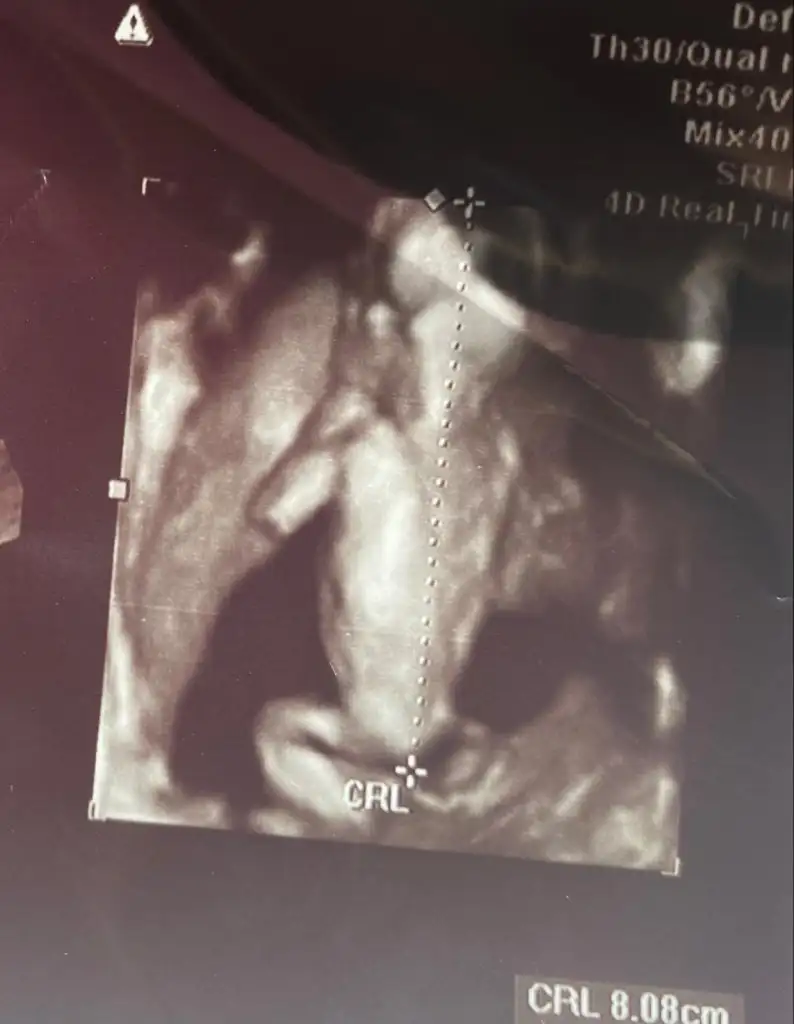

Sırtı dönük üç boyutlu tipe bakın ya😂küçük kurbağam🫶bu arada 16.haftadan önce cinsiyet açıklamayı sevmem ama erkek hani dedi yüksek ihtimalle eşim tekrar sorunca erkek gibi dedi💙

Eveet kızlar ben de doktordan geldim detaylıya girdiğim için çok didikledi beni doktor,burun kemiği var ense kalınğı güzel istediğim gibi dedi,beyini inceledi gördüğüm kadarıyla normal dedi neyse kalpte ki 3damardan 1tanesini göremedi ama haftası küçük dedi ben zorla görmeye çalışıyorum bebeklik bi sorun yok dedi,ben de sıkıntı yapmıyorum şimdilik,harici sıkıntım yok ikili testi ve sıvı aldırmayı kabul etmedim bi kağıt imzaladım sizde de öyle mi oldu,yaaa aşırı hareketliydi yani dört dönüyordu resmen😂